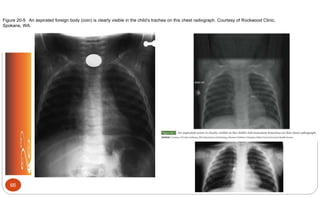

Figure 20-5 An aspirated foreign body (coin) is clearly visible in the child’s trachea on this chest radiograph. Courtesy of Rockwood Clinic,

Spokane, WA.

Foreign Body Aspiration

 Inhalation of any object into

respiratory tract

 7% of deaths (children < 4)

 Manifestations: Coughing, choking,

gagging, hoarse or muffled voice sounds,

difficulty breathing, severe inspiratory

stridor, wheezing, tachypnea, nasal flaring,

retractions, irritability, decreased

responsiveness

 Nursing Management: Assessment,

cardiopulmonary monitoring, remove

foreign body